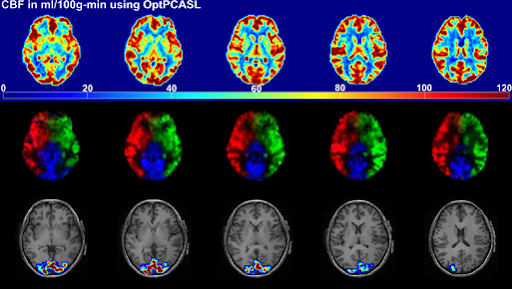

초기의 MRI는 두뇌 각 부위의 정적인 구조만 촬영할 수 있었으나, 1990년대 중반, '기능적 MRI(functional MRI, fMRI)'가 개발되었다.

MRI는 뉴런에 흐르는 전기 신호를 직접 촬영할 수는 없지만, 뉴런에 에너지가 공급되려면 산소가 반드시 있어야 하므로, 혈액 속 감소하는 환원헤모글로빈(reduced hemoglobin)의 자성에 영향받은 수소 양성자를 추적하여, 어떤 자극을 주고 반응하는 두뇌의 다양한 부위들이 상호 작용하는 패턴을 알 수 있게 된 것이다.

fMRI의 이러한 특성을 이용하여 생각의 경로를 추적하면 두뇌 지도 작성(brain mapping) 뿐 아니라, 알츠하이머병, 파킨슨병, 정신분열증 등 다양한 신경질환의 원인과 치료법을 찾아내는데 힌트를 얻을 수 있다.

그리고 두뇌를 이루고 있는 물질의 다양한 성분들은 반복되는 라디오파 펄스에 대해 다르게 반응한다. 따라서 라디오파 펄스의 반복 시간을 바꿔주거나, 시간 차를 두고 90도 각도의 고주파 펄스를 가하거나, 수소 양성자가 방향을 바꾸면서 나오는 에코 영상 획득 시간을 다르게 해줌으로써, 두뇌 안의 특정 구조나 특정 병변이 뚜렷하게 나오는 영상을 얻을 수 있다.